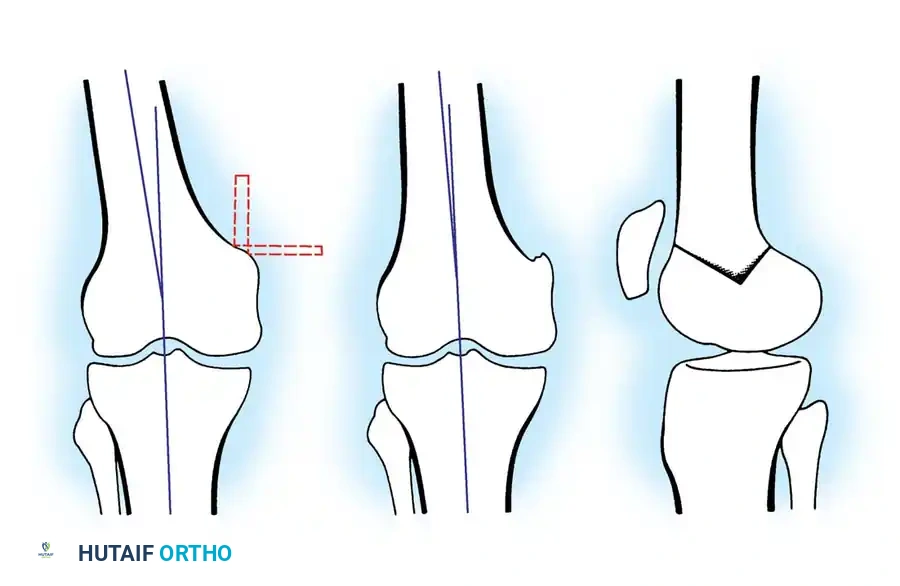

High Tibial Osteotomy (HTO)

HTO is primarily indicated for medial compartment osteoarthritis associated with varus deformity. The goal is to shift the mechanical weight-bearing axis slightly lateral to the midline of the knee joint (the Fujisawa point, typically 62% of the tibial width from the medial edge).

Surgical Approaches:

1. Lateral Closing Wedge HTO: Involves removing a laterally based wedge of bone from the proximal tibia and fixing the osteotomy with a plate or staples. It requires a fibular osteotomy or proximal tibiofibular joint disruption.

2. Medial Opening Wedge HTO: Increasingly popular due to the avoidance of the peroneal nerve and preservation of bone stock. A medial osteotomy is created, opened to the desired correction angle, and stabilized with a rigid locking plate. The void may be filled with allograft or synthetic bone substitute.

Distal Femoral Osteotomy (DFO)

DFO is indicated for lateral compartment osteoarthritis associated with a valgus deformity. Because the deformity in a valgus knee is typically located in the distal femur rather than the proximal tibia, a medial closing wedge or lateral opening wedge osteotomy of the distal femur is performed.

Surgical Atlas: Osteotomy and Realignment Biomechanics

The following radiographic and illustrative figures detail the preoperative planning, biomechanical axes, and intraoperative fixation strategies critical for successful osteotomies around the knee.

Preoperative templating is mandatory. The mechanical axis must be drawn from the center of the femoral head to the center of the ankle mortise. The degree of correction is calculated to ensure the new weight-bearing line passes through the targeted compartment.

Intraoperative fluoroscopy is utilized to confirm the osteotomy trajectory. Guide pins are placed parallel to the joint line, ensuring the hinge point remains intact to provide intrinsic stability to the osteotomy site.